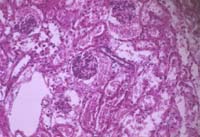

Focus your sample in brightfield.

(Note the dark shadow in the upper right)

Kohler_start.jpg (9093 bytes)